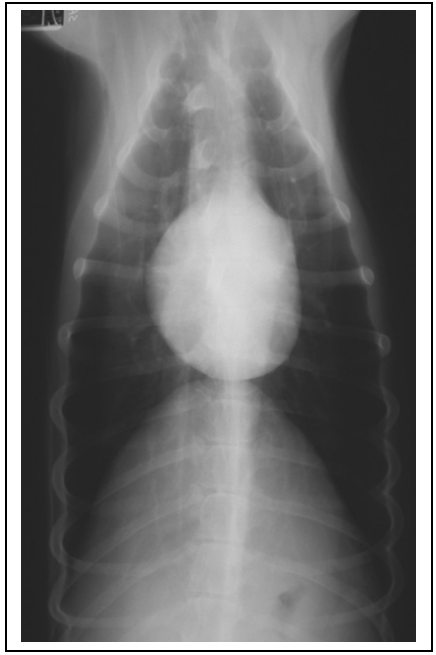

(2)识别胸椎、肋骨、胸骨、横膈外围结构影像(图4-4、4-5、4-6、4-7,注意观片灯评估X线影像时X线片的正确放置)。

(3)识别心脏、大血管、肺脏、气管、支气管影像(图4-4、4-5、4-6、4-7)。

(4)区分右侧位和左侧位以及腹背位和背腹位投照的明显区别(图4-4、4-5、4-6、4-7)。

图4-6正常犬胸部背腹位投照X线片影像 |